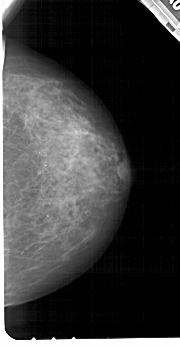

A_1211_1.RIGHT_CC

RIGHT_CC LINES 5176 PIXELS_PER_LINE 2686 BITS_PER_PIXEL 12 RESOLUTION 43.5 NON_OVERLAY